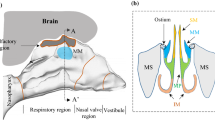

Acoustically driven nebulized drug delivery (acoustic aerosol delivery) is the most efficient noninvasive technique for drug delivery to maxillary sinuses (MS). This method is based on the oscillation of the air plug inside the ostium to transport drug particles from the nasal cavity (NC) to the MS. The larger the wavelength of the air plug oscillation in the ostium, the greater the penetration of drug particles to the MS. However, using this technique, the maximum drug delivery efficiency achieved to date is 5%, which means 95% of the aerosolized drugs do not enter the MS and are wasted. Since the largest amplitude of the air plug oscillation occurs at its resonance frequency, to achieve an improved MS drug delivery efficiency, it is important to determine the resonance frequency of the nose–sinus combination accurately. This paper aims to investigate the impact of geometrical parameters on the resonance frequency of the nose–sinus model. Both experimental and computational acoustic models, along with the theoretical analysis, were conducted to determine the resonance frequency of an idealized nose–sinus model. The computational modeling was carried out using computational fluid dynamics (CFD) and finite element analysis (FEA), whereas in the analytical solution, the mathematical relationships developed for a conventional Helmholtz resonator were employed. A series of experiments were also conducted to measure the resonance frequency of a realistic NC–MS combination. The results demonstrated a good agreement between the experimental and CFD modeling, while the FEA and theoretical analysis showed a significant deviation from the experimental data. Also, it was shown that the resonance frequency of the idealized nose–sinus model increases by up to twofold with increasing the ostium diameter from 3 to 9 mm; however, it has an inverse relationship with the ostium length and sinus volume. It was also reported that the resonance frequency of the nose–sinus model is independent of the NC width and MS shape.

Pourmehran, O., Arjomandi, M., Cazzolato, B. et al. The impact of geometrical parameters on acoustically driven drug delivery to maxillary sinuses. Biomech Model Mechanobiol 19, 557–575 (2020). https://doi.org/10.1007/s10237-019-01230-5